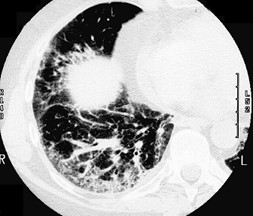

隐源性机化性肺炎(Crytogenic organizing pneumonia COP),是病因不明的肺间质炎症和纤维增生,向肺泡蔓延,导致肺泡逐渐填满蛋白质、成纤维细胞和纤维。症状是干咳、呼吸困难、发烧、全身不舒服。CT可以发现弥漫性实变、玻璃样浸润、弥漫性纤维化。与其它疾病如癌症、结缔组织病相关的,叫继发性机化性肺炎(Secondary organizing pneumonia)。究竟什么引发了这些病理改变不清楚。和其它原因不明的间质性肺炎不同,机化性肺炎肺脏的结构没有被破坏,及时治疗肺脏可能恢复正常。

第12天我接手,只管一天,代别人班。读完逐日志,发现肺科医生计划当天把甲基强的松龙降到40毫克静脉注射,每天两次。查完房,回头再把记录、化验、药物、氧气需要量读了一遍, 把CT翻来覆去看了两遍。 我认为这个病人是COP。 肺科医生上了皮质激素,是正确的措施。 但是剂量不够大,更不应该现在就减量。